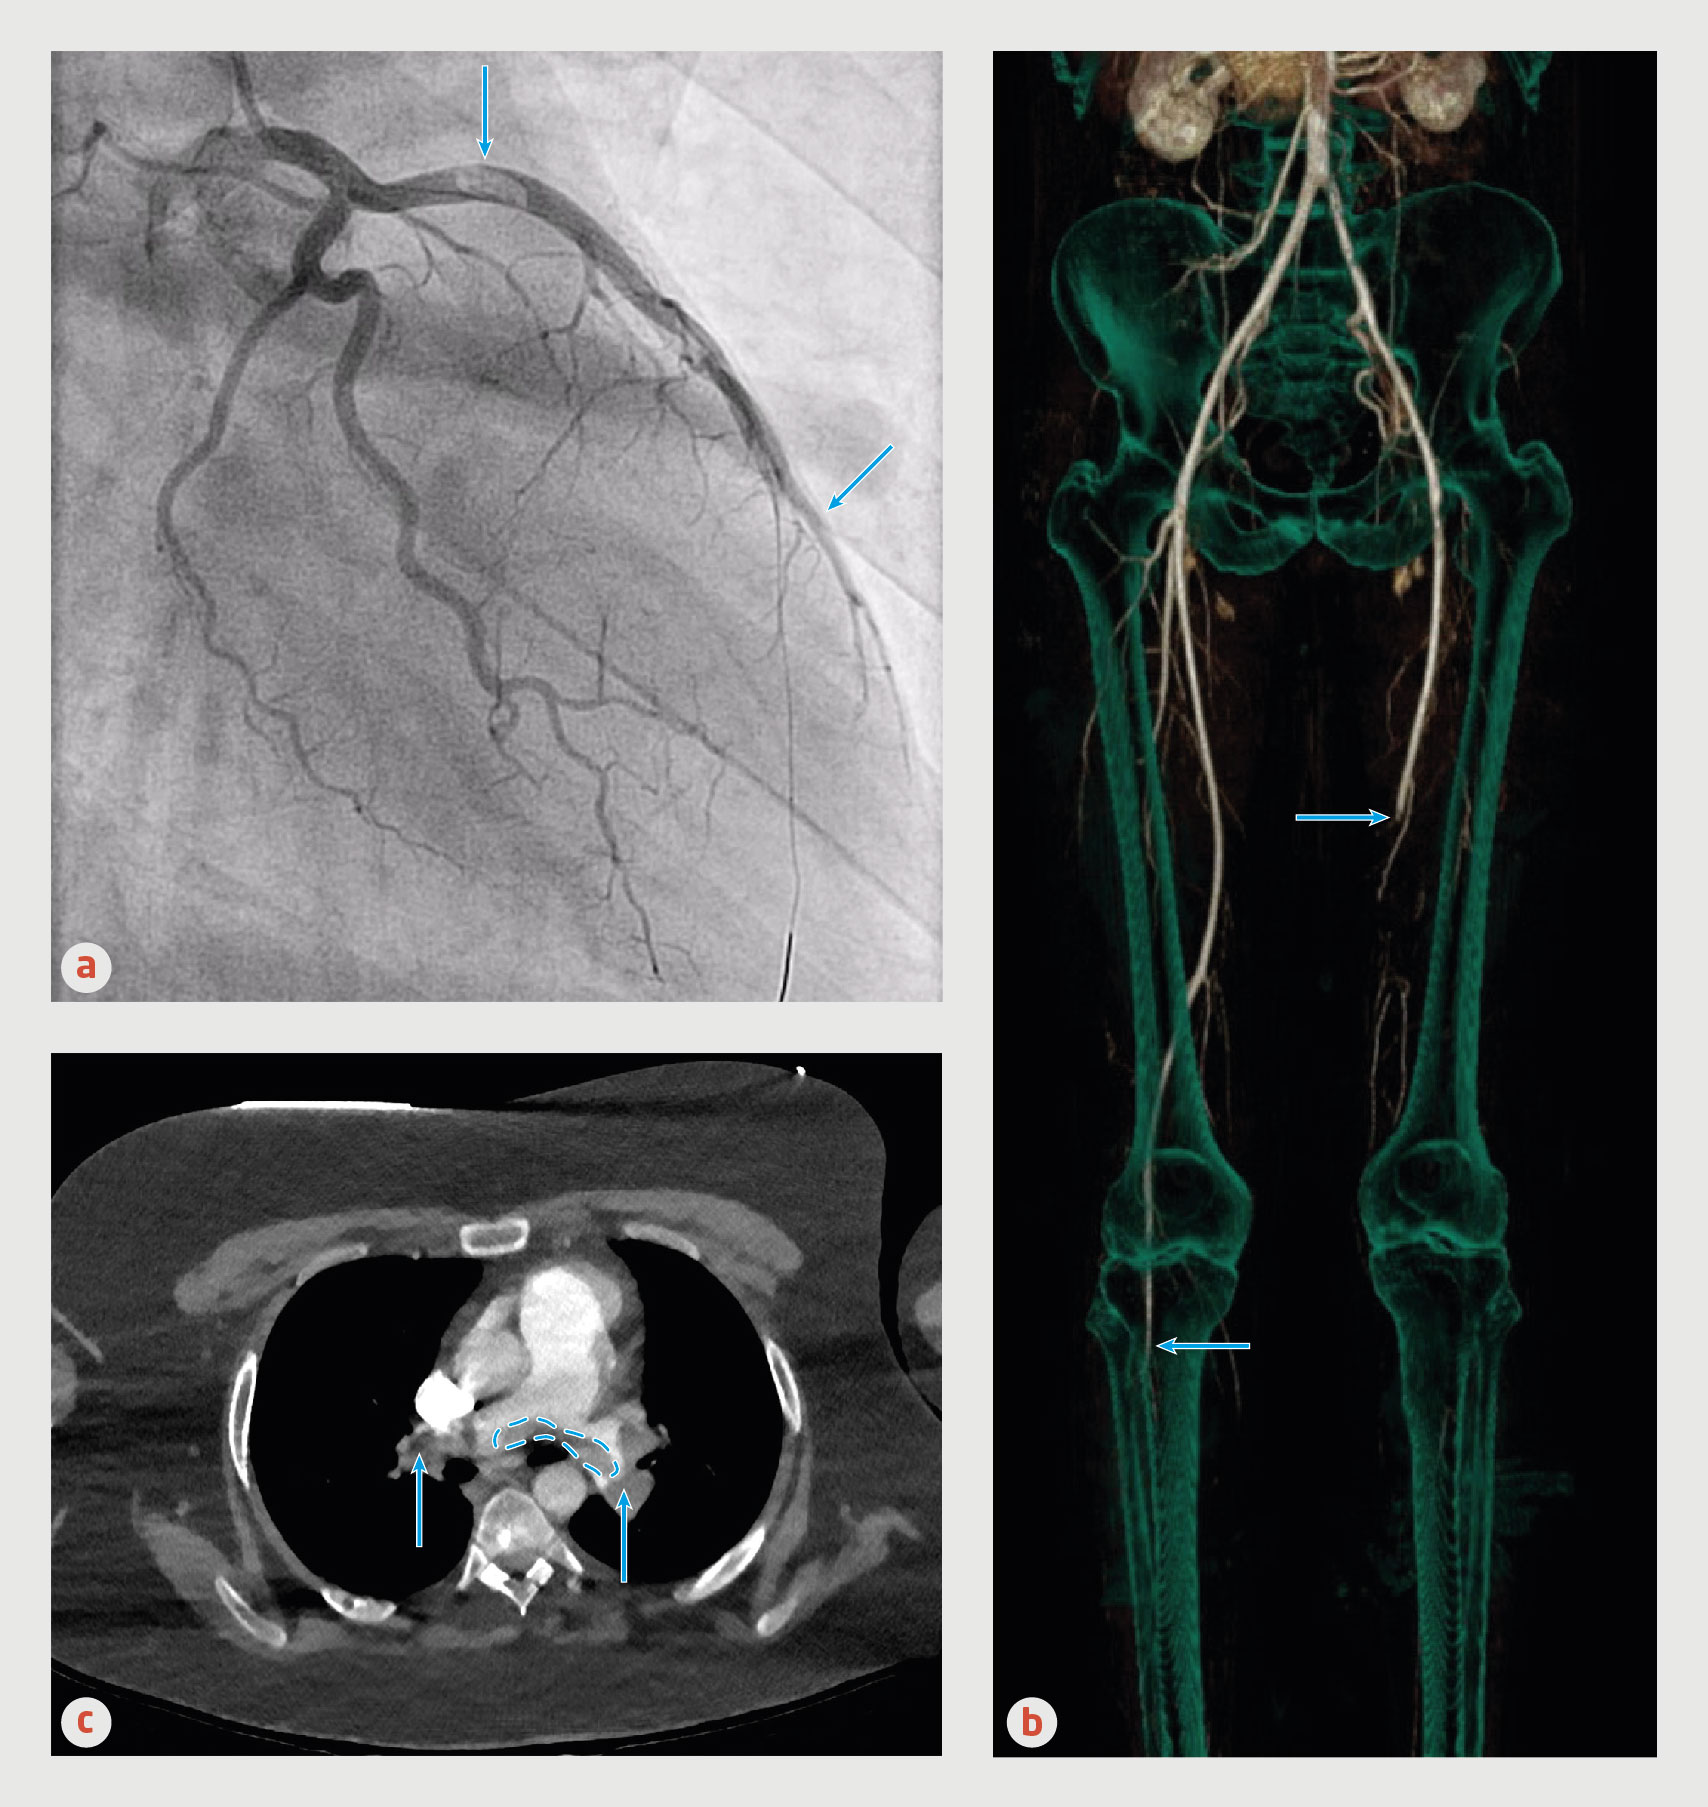

Toxicologische screening van de urine is negatief voor andere drugs, inclusief cocaïne. Het ecg laat een acuut voorwandinfarct zien (figuur 1). Bloedonderzoek toont een homocysteïneconcentratie van 205 μmol/l en vitamine B12-concentratie van 114 pmol/l (tabel 1). Bij coronaire angiografie (CAG) zien wij een trombus proximaal in de ramus interventricularis anterior van de linker coronairarterie (‘left anterior descending artery’; LAD) en een trombotische occlusie distaal in deze arterie (figuur 2a en video 1).

Figuur 2

Trombo-embolieën van patiënt A, B en C

Figuur 2 | Trombo-embolieën van patiënt A, B en C

(a) Coronair angiogram van patiënt A. Proximaal in de ramus interventricularis anterior van de linker coronairarterie (‘left anterior descending artery’) is een grote trombus zichtbaar (pijl) met distaal een trombotische occlusie van deze arterie (pijl). (b) CT-angiografie van de buik-, bekken- en beenvaten van patiënt B. Aan de rechterzijde is een occlusie zichtbaar vanaf de crurale arteriën (pijl). Aan de linkerkant is de distale A. femoralis superficialis (pijl) geoccludeerd en is de A. femoralis profunda over het gehele traject dicht. In de A. femoralis superficialis en de A. iliaca communis aan linkerzijde zijn trombi zichtbaar. (c) Transversale opname van een CT-angiografie van thorax van patiënt C. Zowel in de linker als de rechter A. pulmonalis zijn obstruerende trombi aanwezig (pijlen). In de bifurcatie van de Aa. pulmonales is een trombus zichtbaar (omlijnd), passend bij een ruiterembolus.